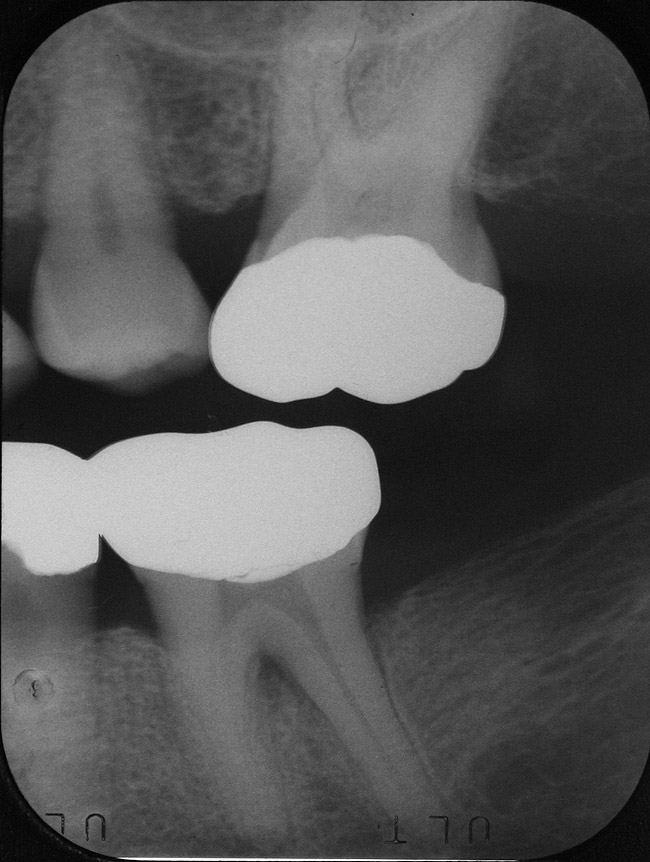

Inflammation limited to soft tissues around a dental implant may result from dental plaque colonization and is termed peri-implant mucositis. This is a reversible inflammatory condition limited to the soft tissues around the implant (without any bone loss), analogous to gingivitis around natural teeth. A diagnosis of peri-implantitis results when the inflammation spreads apically, causing progressive loss of osseointegrated supporting bone, analogous to periodontitis around natural teeth16 (Figure 2A and Figure 2B). It is essential for practitioners to be familiar with these diagnostic terms when assessing the long-term success of implants and peri-implant health (Table 1).

Figureb 2  (A) Clinical and (B) radiographic views of implants at site Nos. 30 and 31 demonstrating bone loss caused by peri-implantitis after 8 years in function. Note gingival inflammation and plaque accumulation around implants.

Figure 2b